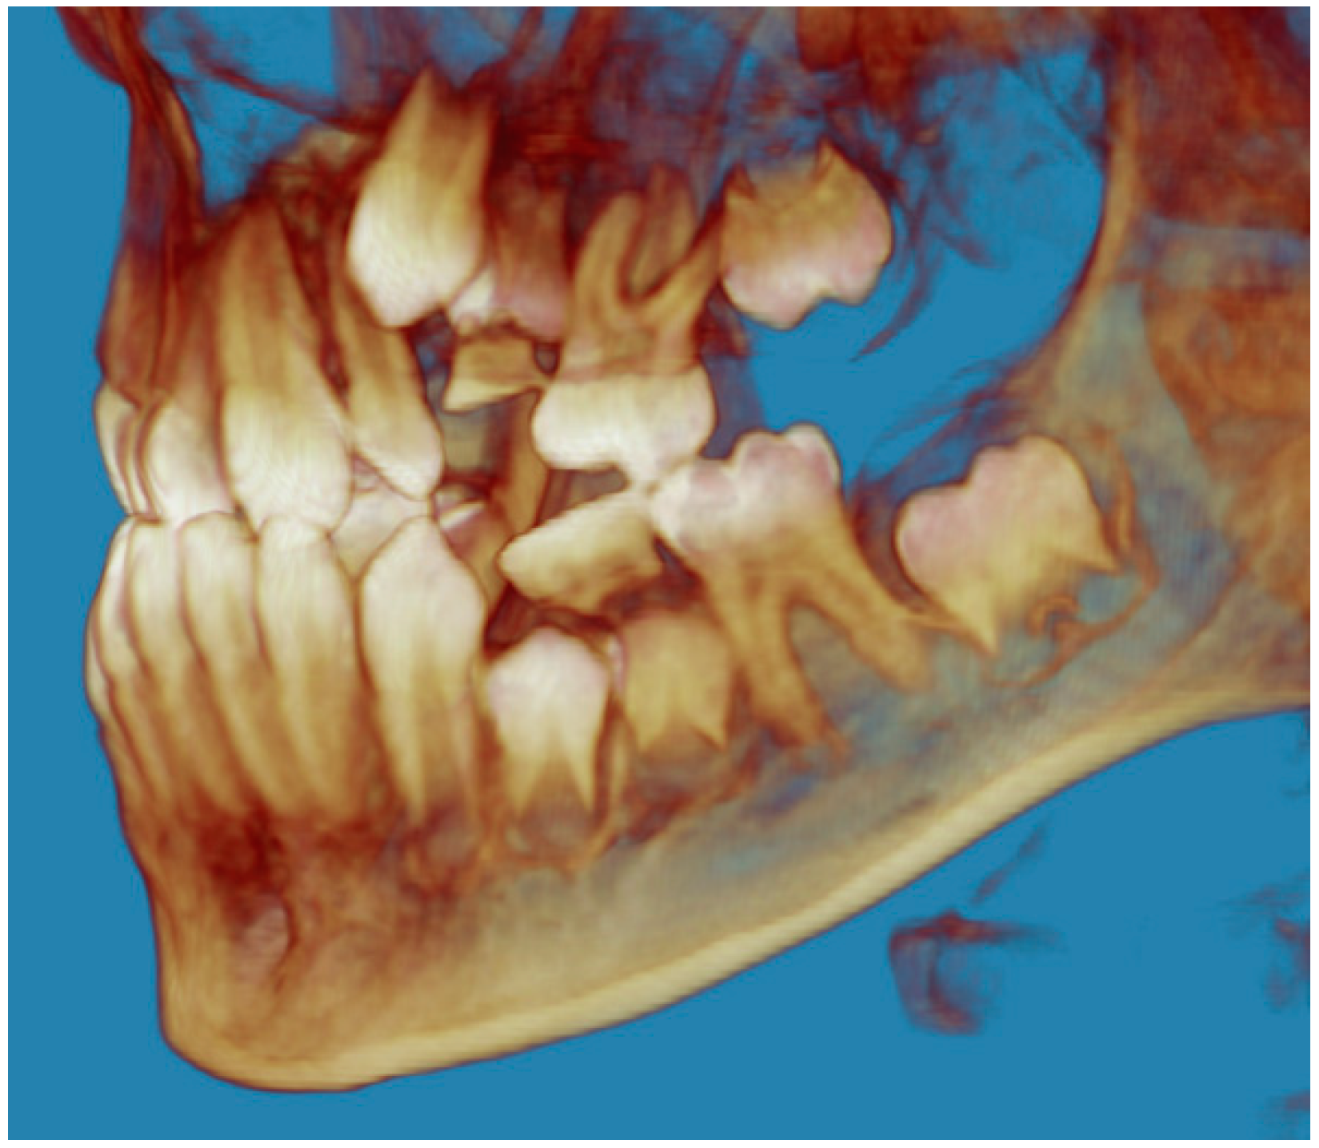

- Evaluation of impacted teeth, a common indication of CBCT in orthodontics. The advantages of CBCT include assessment of the tooth location and position, the stage of development, and status of adjacent teeth. CBCT is justified in these cases, because CBCT has the capability of evaluating the impacted teeth and adjacent structures more accurately than 2D conventional imaging. The benefit–risk ratio is favorable, especially if the CBCT volume is collimated to the impacted tooth. Figure 1, Figure 2, Figure 3 and Figure 4 show an example of impacted maxillary canines, and their proximity to the maxillary lateral incisors. Figure 1 shows an intraoral photograph. The benefit of CBCT acquisition in this case includes the ability to visualize the canines and the lateral incisors in three dimensions, which can be visualized in Figure 2 and Figure 3. In this case, the maxillary right lateral incisor exhibited external root resorption, a finding that would be difficult to see on a conventional 2D panoramic radiograph. Figure 4 shows a Maximum Intensity Projection of a panoramic view derived from the CBCT volume. This unique view is free of magnification, distortion, ghost images, and overlaps frequently seen in conventional 2D panoramic radiography.